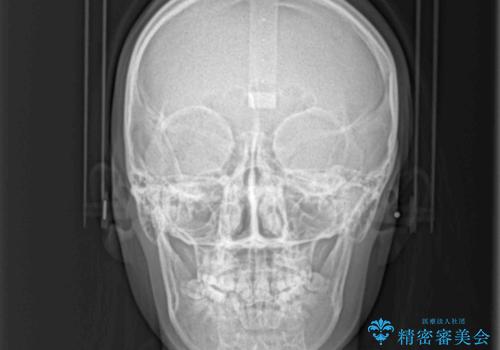

- 前歯の著しい叢生とクロスバイトを気にして来院された患者様です。

叢生が強いため、一見すると抜歯矯正と判断したくなりますが、下顎臼歯が舌側に倒れていることから、上顎骨を側方拡大し、非抜歯矯正の可能性を検討することとしました。

急速拡大装置による上顎骨の側方拡大が思った以上にうまくいき、非抜歯での矯正が可能となりました。